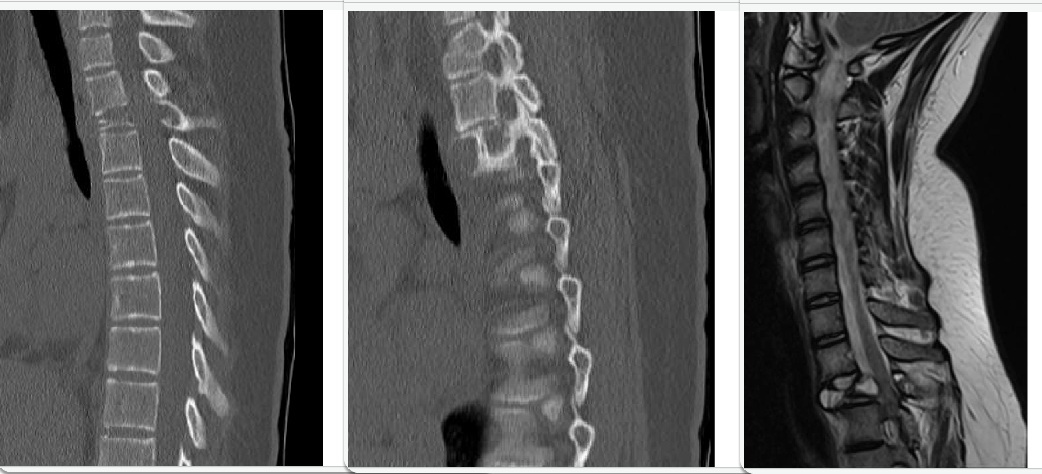

Seorang anak perempuan berusia 14 tahun yang sebelumnya sehat datang ke ruang gawat darurat dengan riwayat beberapa bulan lalu mengalami nyeri pada regio punggung bagian atas. Dia mengatakan bahwa nyeri membaik saat berbaring dan memburuk saat berdiri tegak. Dia menyangkal adanya nyeri menjalar, mati rasa, kesemutan atau ada hubungannya dengan saluran cerna atau berkemih. Riwayat trauma negatif. Hasil imaging terlampir. Apakah pengobatan yang paling mungkin diterapkan pada pasien :

D. Reseksi dan stabilisasi dengan instrumen

This lesion has imaging characteristics most consistent with an aneurysmal bone cyst. These include radiolucent, lytic destruction on CT with septations, high signal intensity on T2 weighted images and double density fluid levels. Aneurysmal bone cysts are benign tumors, and may often arise within another bony tumor. The indicated treatement is for resection of the lesion and subsequent stabilization of the spine, especially in a case like this, with vertebra plana. Antibiotic therapy, chemotherapy and radiation therapy are not indicated for this lesion. Biopsy of this lesion will not contribute to its definitive surgical management.